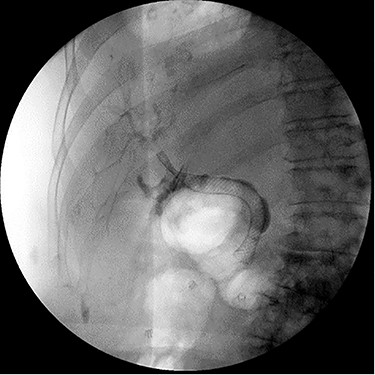

Intraoperatively, a distended, friable, gangrenous gallbladder was encountered, requiring conversion to open procedure. A Strasburg Type D partial laceration to the common bile duct (CBD) was confirmed with intraoperative cholangiogram and repaired primarily over a T-tube. A Jackson-Pratt (JP) drain was placed near the repair (Fig. 1).

Intraoperative cholangiogram demonstrating Strasburg Type D BDI [1].